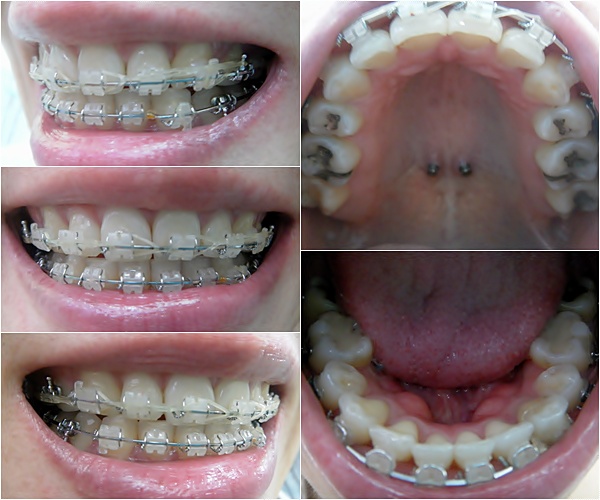

오라픽스 3D 개인맞춤 치아교정장치 붙이고 나서 월치료~

오라픽스장치 월치료는 일반장치 월치료랑 비슷하게~

와이어 바꾸고 파워체인 새로 연결하는 걸로~ 진료 끄읕~ ^**^

그리고 27번째 월치료는요~ ' ㅁ')//

제 치아에 맞게 맞춘 오라픽스장치를 붙이니 세라믹장치 붙였을 때 보다

더 섬세한 진료가 가능한 거 같아요~ + ㅁ+)b 우왕 굳~!

두꺼운 와이어로 교체하고 파워체인 연결하고~